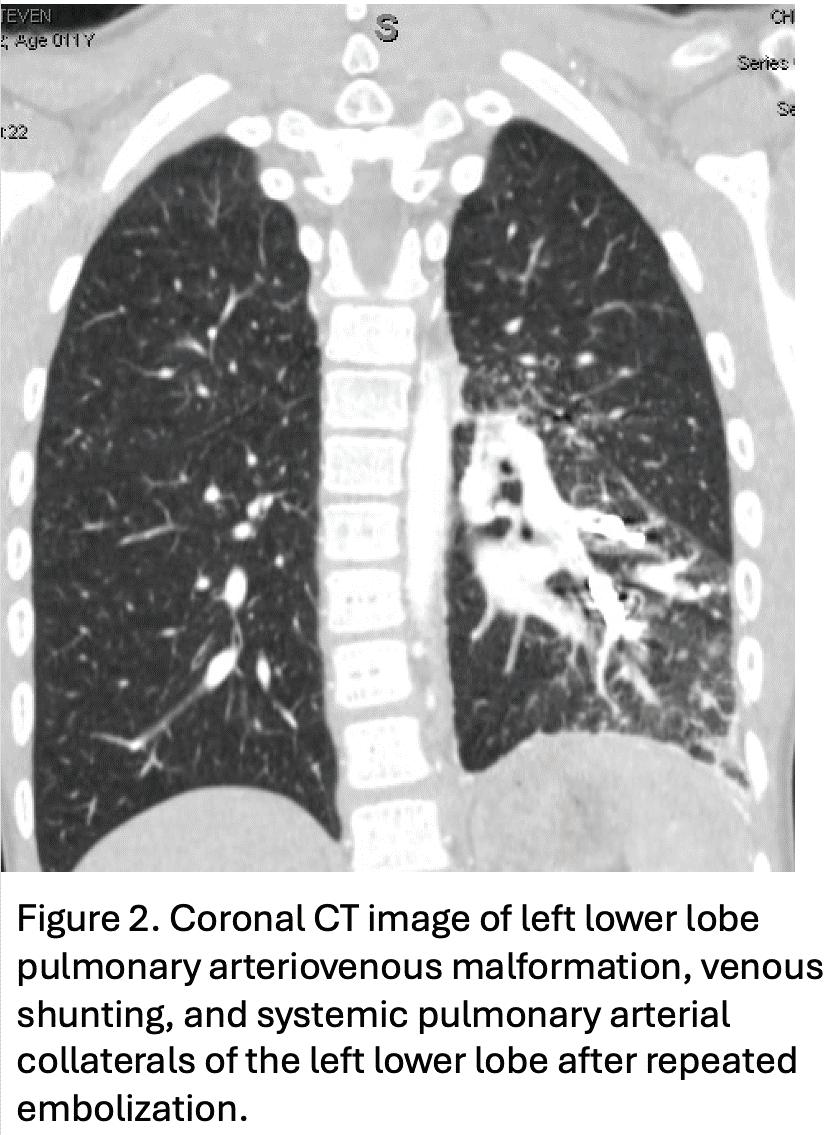

few complex procedures including an endobronchial carcinoid tumor requiring a sleeve lobectomy (Fig 1) and a pulmonary arteriovenous malformation with extensive large collaterals that had failed multiple embolization attempts and required left lower lobectomy (Fig 2). Rather than perform these extremely complex and high-risk procedures with a relatively new team at Children’s, we elected to perform these cases at the adult hospital. We believed this approach accomplished our goal of expanding the MIS options available to these children while simultaneously adding to the experience for the pediatric surgeon who was still able to participate in the operation at Froedtert.

Utilizing this framework of collaboration and shared expertise has allowed for the successful development of a pediatric robotic surgery team over the course of the last year. Since April 2024 we have completed 7 collaborative robotic thoracic cases in our pediatric patients, with 5 of them occurring at Children’s Wisconsin (Table 1). Our approach, emphasizing safety and progressive skill expansion in the setting of institutional collaboration, has strengthened the robotic surgery teams across both medical centers. As technology advances (and downsizes) we can expect a broader application of these techniques, ultimately improving outcomes for our youngest patients and we are proud to be leading the way.